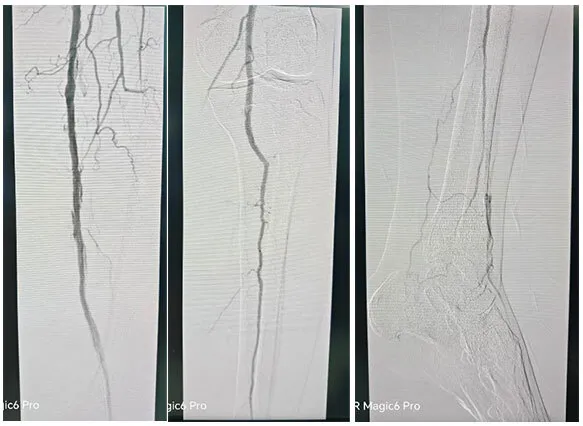

术å‰è¯Šæ–­åQšæœ¯å‰CTAæç¤ºåŒä¸‹è‚¢åŠ¨è„‰å×I漫èÊYæ–‘å—ã€é’™åŒ–æ–‘å—ã€æØœåˆæ–‘å—,½Ž¡è…”ä¸åŒ½E‹åº¦ç‹­çª„åQ›å³é«‚内动脉ã€å³è‚¡åŠ¨è„‰ã€åŒä¾§é¢ˆåŽåŠ¨è„‰ã€èƒ«å‰åŠ¨è„‰å±€éƒ¨é—­å¡žã€?/p>

手术˜q‡ç¨‹åQšæœ¯ä¸­é€ åª„½Cø™‚¡‹¹?è…?è†ä¸‹èŠ‚æ®µæ€§ç‹­½H„闭塞,多å‘é’™åŒ–ã€‚ä¿æŠ¤ä¼žä¸‹å‡å®¹ï¼Œä½†è¡€½Ž¡é’™åŒ–局部难以推˜q›ï¼Œå‡å®¹¾l“æŸåŽï¼Œäºˆä»¥¾U¦æŸåž‹è¯ç‰©çƒå›?*150mmã€?*200mm全程处ç†åQŒéž˜å†…造媄昄¡¤ºç‹­çª„ŒDµå®Œå…¨å¤é€šï¼Œå†…膜光整åQŒè¡€‹¹é€šç•…åQŒæœªè§é€ åª„å‰‚å¤–æ¸—ï¼Œæœªè§æ˜Žæ˜¾æ “å¡žã€‚æ‰‹æœ¯é¡ºåˆ©ï¼Œæœ¯åŽæ‚£è€…安˜q”ç—…æˆÑ€?/p>